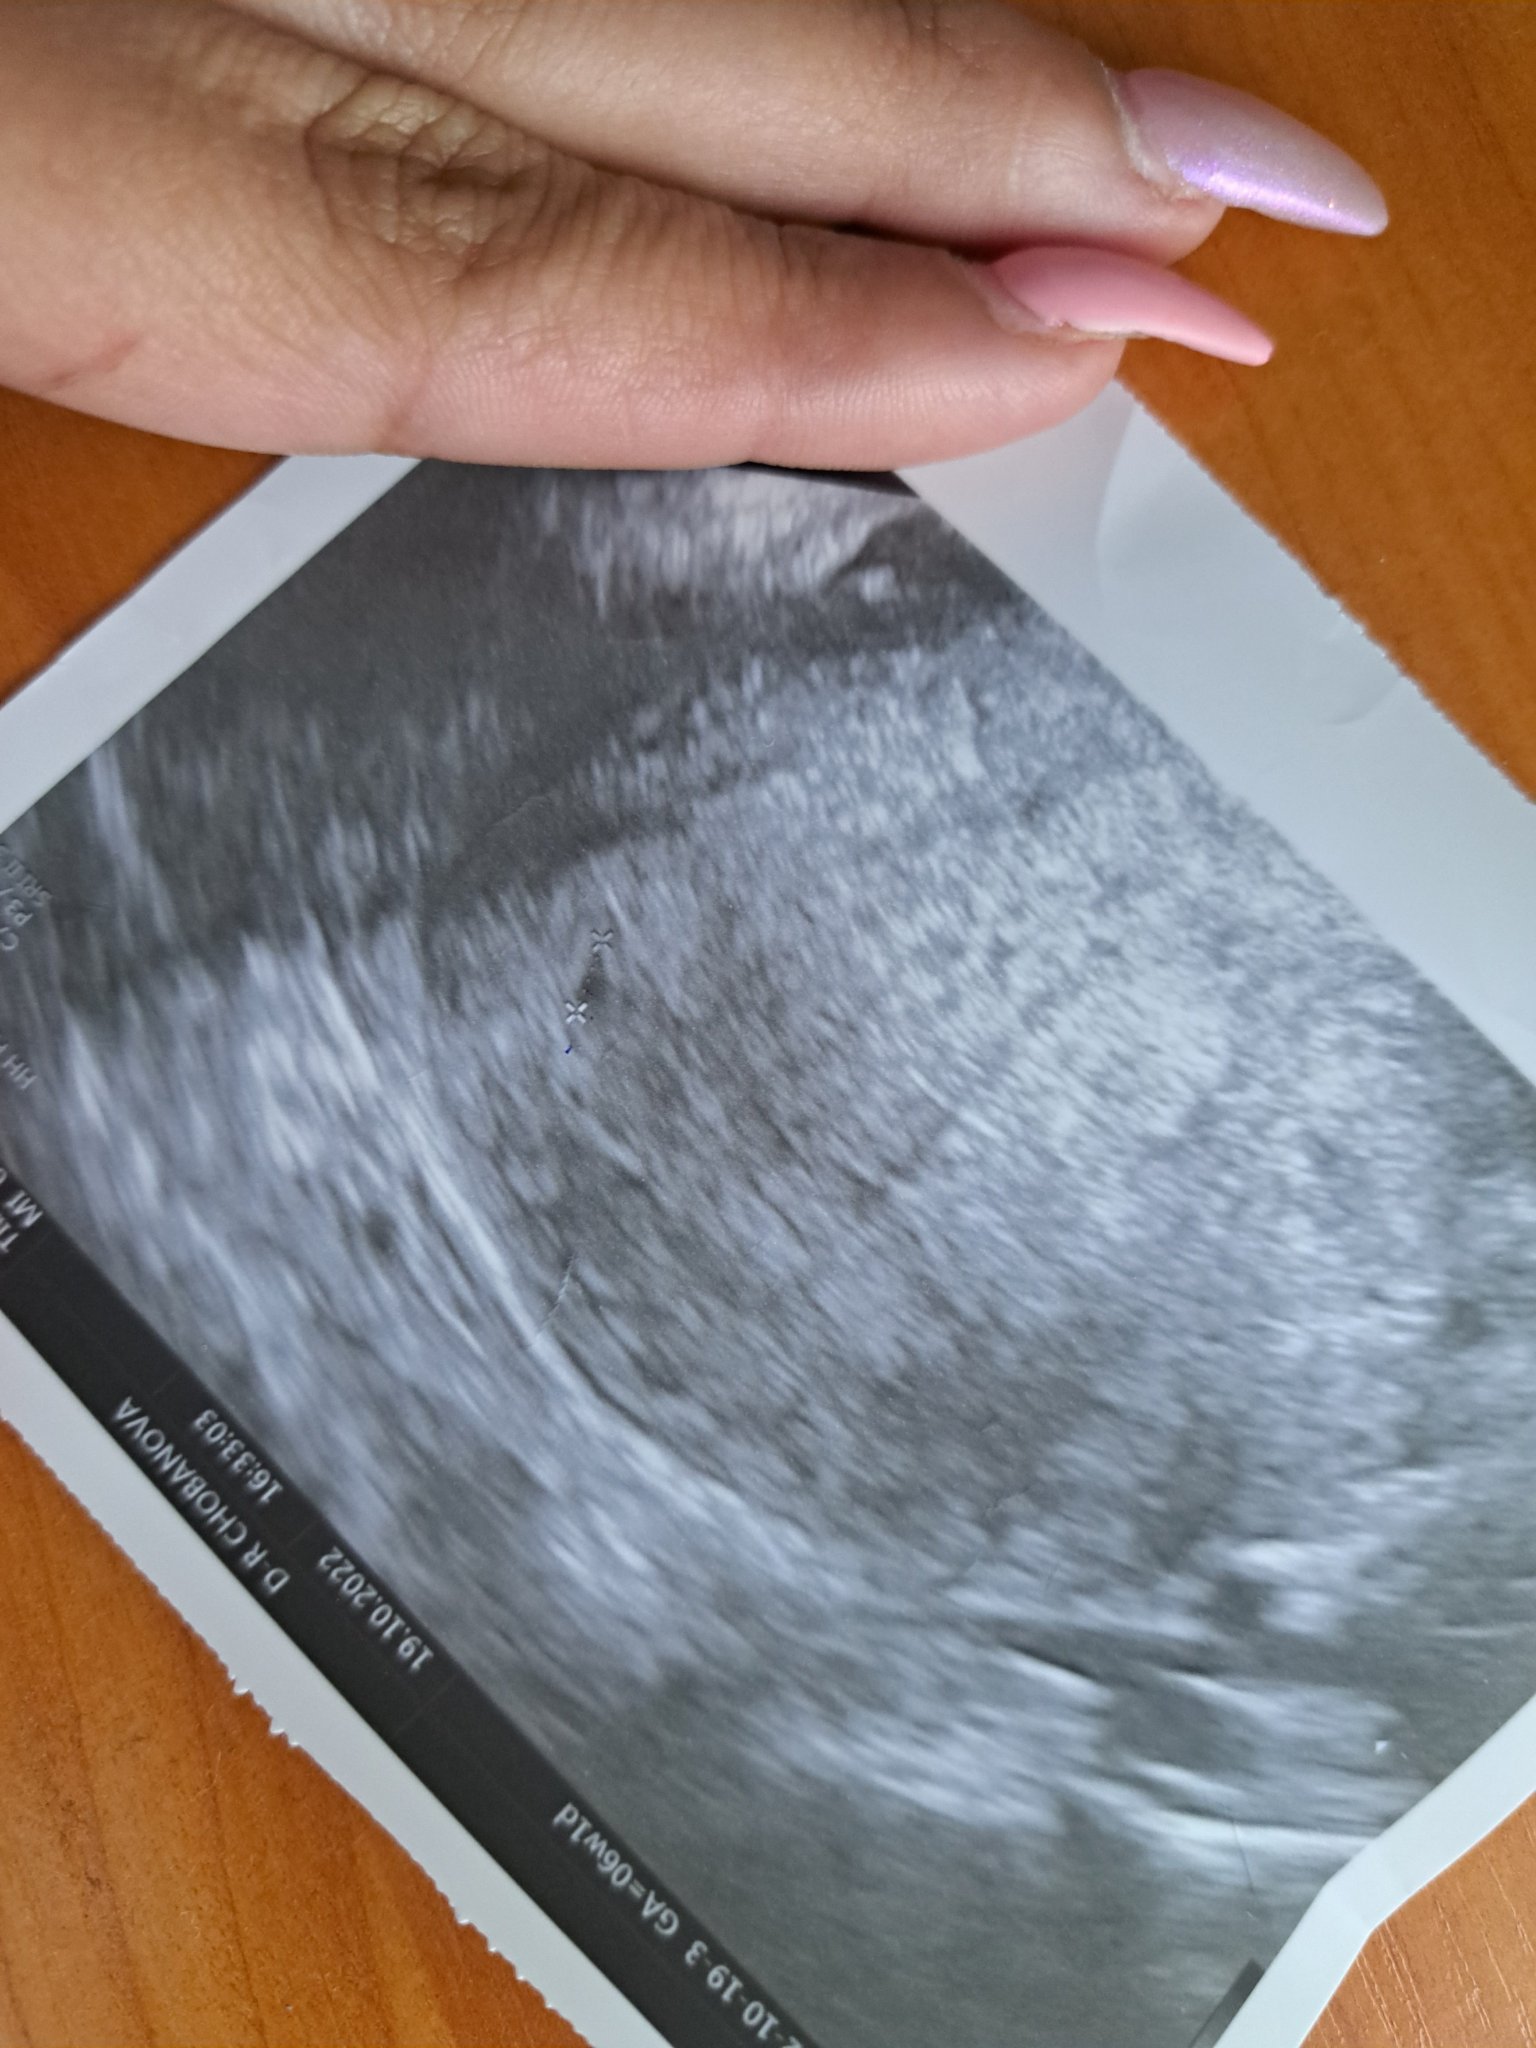

Здравей дами аз искам да ве попитам днеска бях на гинеколок и на видеозона имаше точица  бремена съм какво е вашето мнение  на тази точица

Лили, дай повече информация. Редовен ли ти е цикълът и колко дни е? По последна менструация трябва да си в 6та седмица, обаче тази точка е много малка. Какво ти каза лекарят?